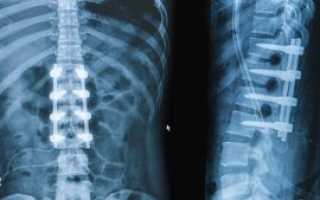

Для стабилизации деформированных позвоночных сегментов проводится операция, во время которой на позвоночный столб крепятся титановые пластины или другие металлоконструкции.

- Транспедикулярная стабилизация. С помощью специальной ножки (педикулы) в смежные позвоночные тела вставляется корригирующая металлическая конструкция в виде винтов, крепко соединенных между собой штангами. Подобная техника чаще всего применяется при смещении или переломе позвонков.

- Транскутанная фиксация. Суть данной операции заключается в следующем. Через небольшой разрез в травмированный сегмент позвоночника вводится зонд, с помощью которого происходит вживление в костные структуры стабилизирующего импланта. Благодаря тому, что стабилизация проводится транскутанно (через кожу), данная техника является наиболее безопасной.

Техника стабилизации поврежденных позвонков подбирается специалистом в индивидуальном порядке, учитывая множество факторов: тип повреждения, возраст и состояние здоровья пациента, наличие противопоказаний. Для операции могут применяться различные металлоконструкции: винты, пластины, стержни, скобы.

На протезированном уровне производится транспедикулярное закрепление позвонков спицами, винтами, пластинами.